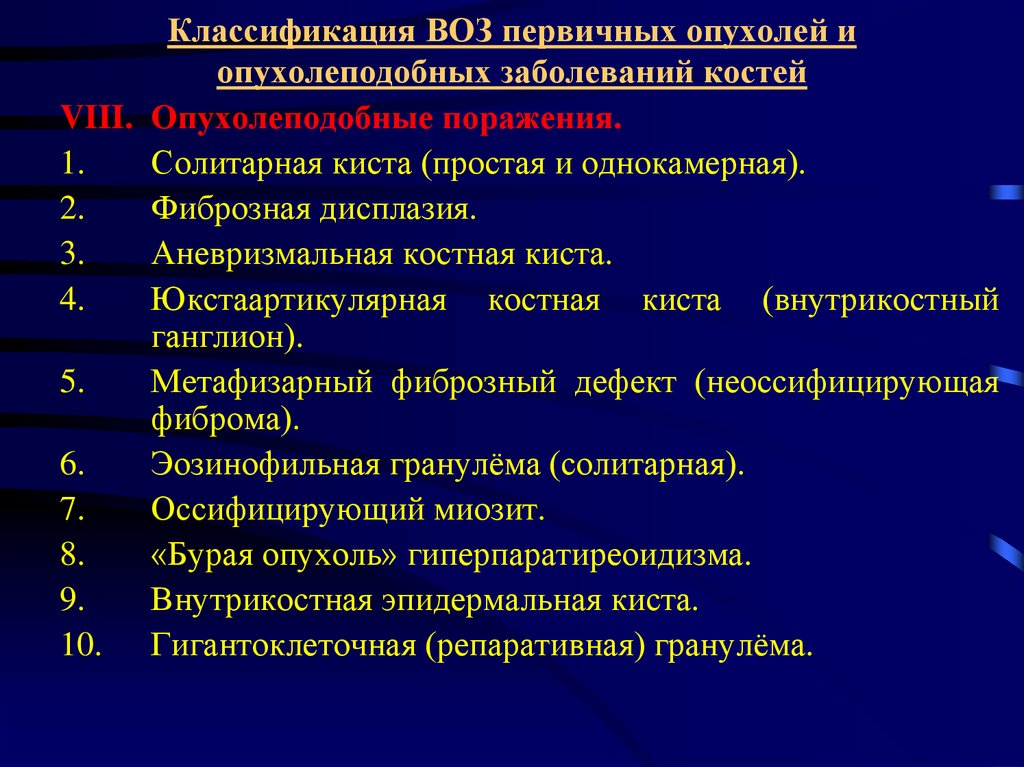

Мрт головного мозга с контрастированием. Мрт с контрастированием опухоль. Мрт головы с контрастом. Магнитно резонансная томография с контрастом головного мозга. Классификация опухолей. Классификация новообразований. Классификация опухолей по воз. Классификация воз опухолей костей.

Классификация опухолей. Классификация новообразований. Классификация опухолей по воз. Классификация воз опухолей костей. Опухоли головки поджелудочной железы классификация. Доброкачественная опухоль поджелудочной. Доброкачественная опухоль поджелудочной железы. Гистологическая классификация опухолей поджелудочной железы.

Доброкачественная опухоль кости классификация. Классификация опухолей и опухолеподобных поражений костей. Классификация опухолей воз. Опухолеподобные заболевания костей.

Доброкачественная опухоль кости классификация. Классификация опухолей и опухолеподобных поражений костей. Классификация опухолей воз. Опухолеподобные заболевания костей. Глиобластома головного мозга мрт. Менингиома головного мозга мрт. Менингиома грейд. Опухоли мозга (менингиома);.